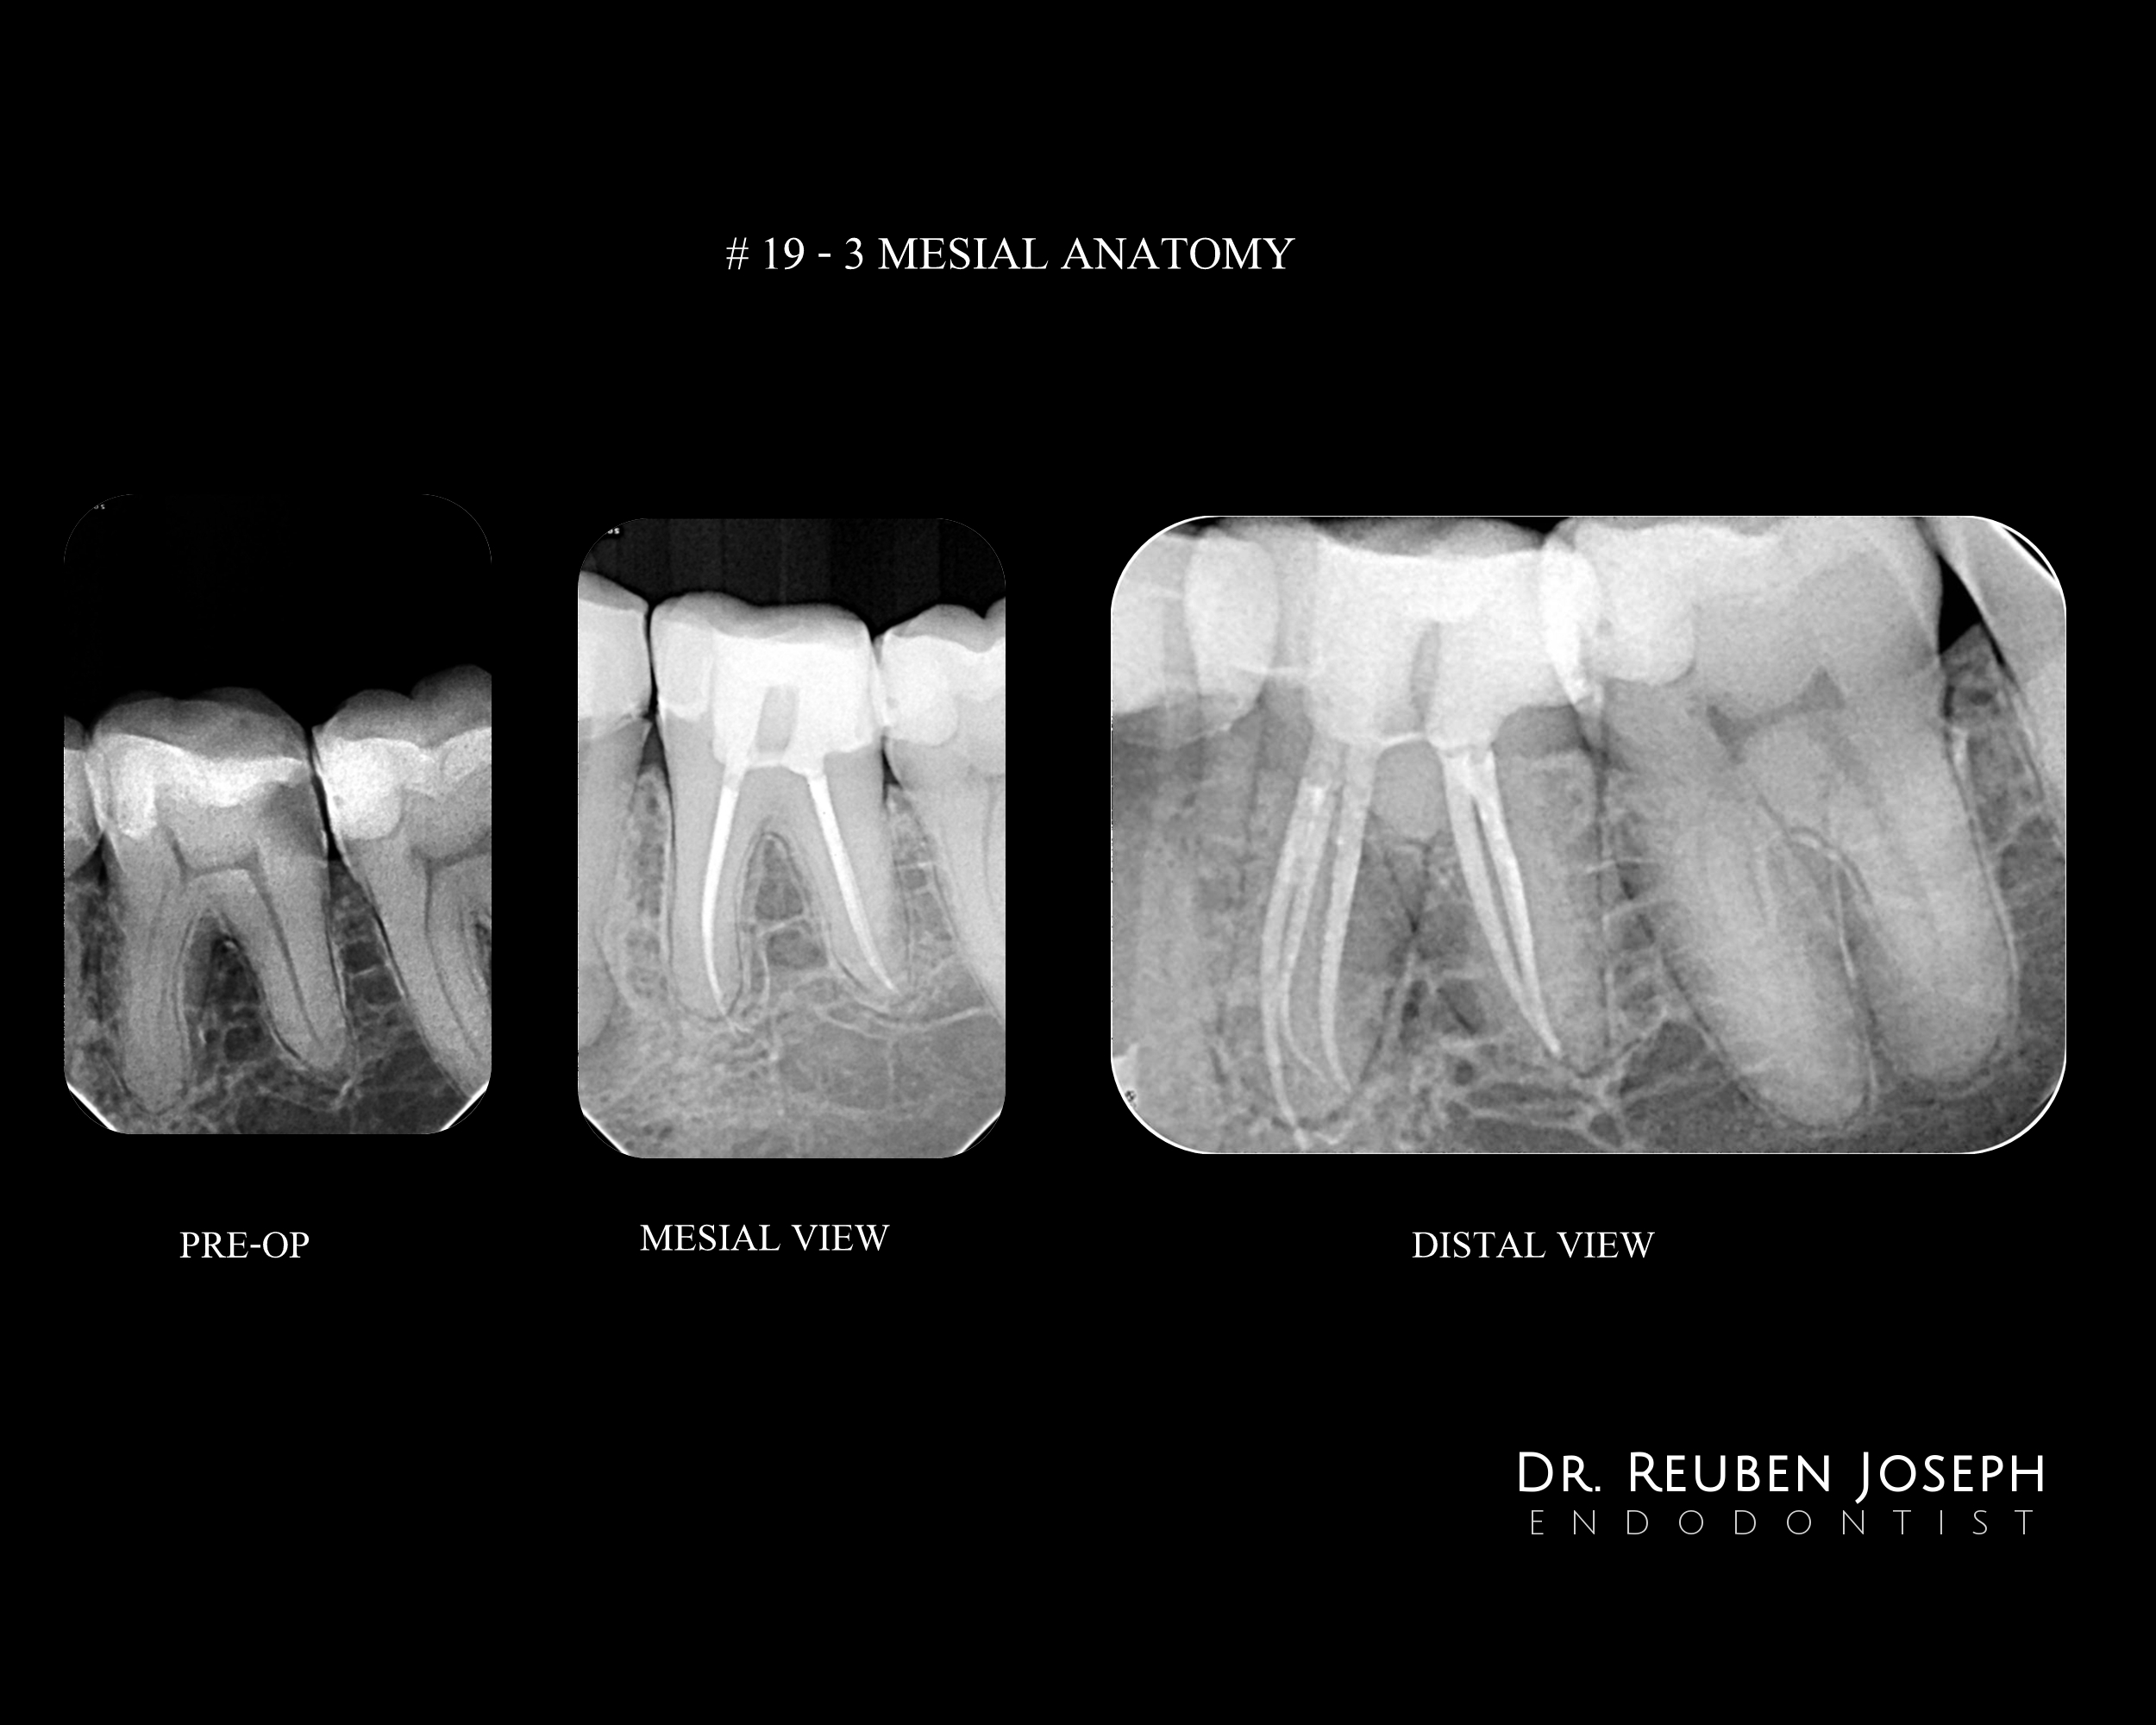

#19 RCT – 3 Mesial Anatomy – Truss Access

U-File pre-bent and customized to cleanunder the truss